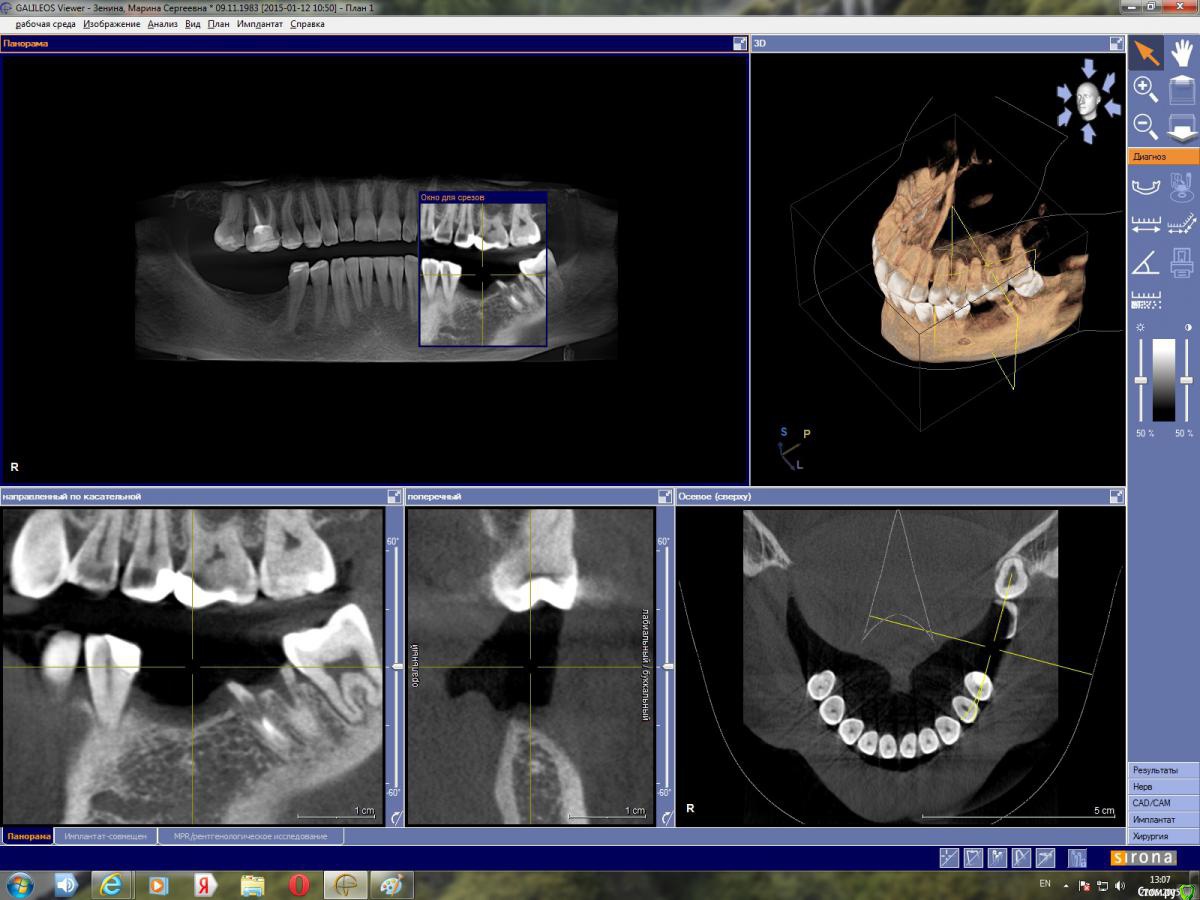

марин зенина Опубликовано 17 января, 2015 Автор Поделиться Опубликовано 17 января, 2015 https://yadi.sk/d/gpmuDkTXdwj3M архив моей КТ вместе с программой для просмотра GalileosViewer. Посмотрите, пжста, можно ли здесь обойтись без костной пластики. Ссылка на комментарий

марин зенина Опубликовано 21 января, 2015 Автор Поделиться Опубликовано 21 января, 2015 пожалуйста, подскажите нужно ли здесь наращивание кости) Ссылка на комментарий

Большой Зеленый Опубликовано 21 января, 2015 Поделиться Опубликовано 21 января, 2015 пожалуйста, подскажите нужно ли здесь наращивание кости)Нарежте скриншотов и выложите сюда.Никто не станет качать столько ненужной информации. Ссылка на комментарий

марин зенина Опубликовано 22 января, 2015 Автор Поделиться Опубликовано 22 января, 2015 выкладываю скриншоты) Ссылка на комментарий

марин зенина Опубликовано 22 января, 2015 Автор Поделиться Опубликовано 22 января, 2015 так? Ссылка на комментарий